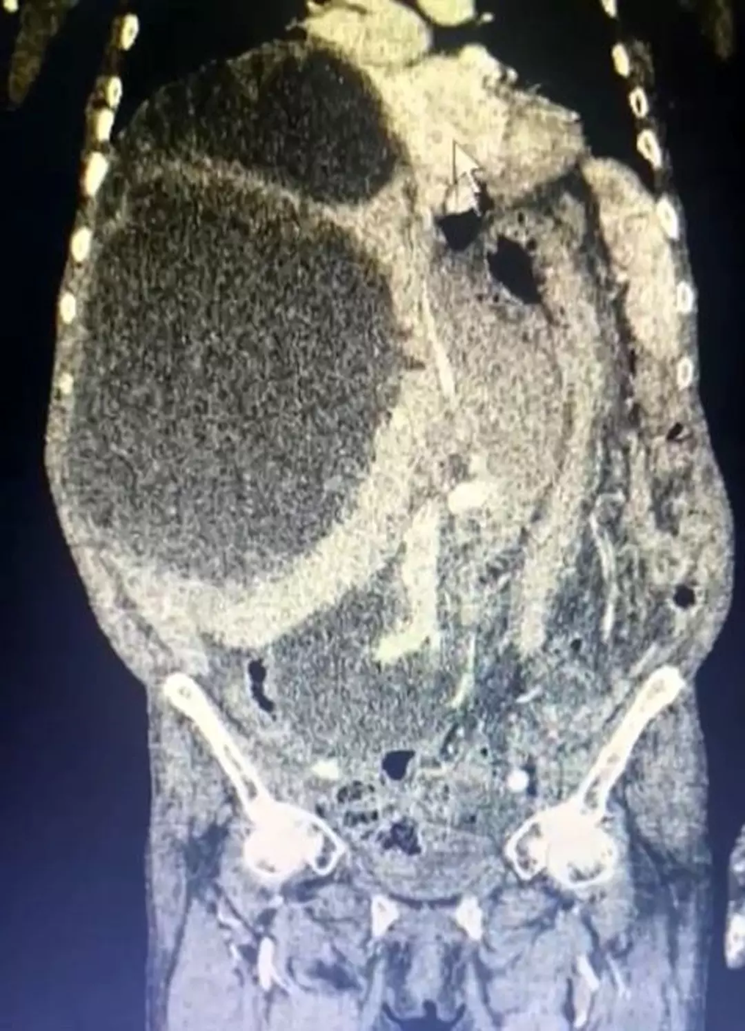

Gümüşhane’de yaşayan, 76 yaşında ve çiftçilik ile uğraşan Asiye Taşdelen karnındaki ağrılara şişlikte eklenince Trabzon Kanuni Eğitim ve Araştırma Hastanesi'ne başvurdu. Doktorların yaptığı tetkikler sonucunda Taşdelen’in karaciğerinde 90 santimetreye ulaşmış bir kist olduğu fark edildi. Tıp tarihine geçen bu büyüklükteki kist sadece hastayı değil doktorları da şok etti. Kedi ve köpeklerden insanlara bulaşan bu kiste karşı doktorlar vatandaşları uyarıyor.

Karaciğerinde 90 santimetreye ulaşarak karnını kaplayan 3 ayrı kedi-köpek kisti tespit edilen kadın hem Gümüşhane’nin hem de tıp dünyasının tarihine geçti. Daha önce bu büyüklüğe ulaşmış bir kedi-köpek kisti görmediklerini dile getiren Genel Cerrahi Uzmanı Operatör Dr. İsmet Çelik,

"Dünya literatüründe 90 santimetreye ulaşarak tüm karnı dolduran kist görmedik. Ameliyatımız 2 saat sürdü" diye konuştu.

Asiye Taşdelen için gerekli tüm tetkikler tamamlandıktan sonra ameliyat kararı verildi. Ameliyatı gerçekleştiren Genel Cerrahi Uzmanı Operatör Dr. İsmet Çelik ve Gastroenteroloji Uzmanı Doç. Dr. Aydın Aktaş tarafından kistlerin 2'si çıkarılırken 1'inin içi boşaltılarak kontrol altına alındı.